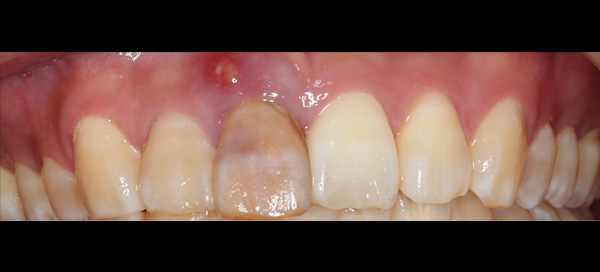

| 年代・性別 | 30代 男性 |

|---|---|

| 主訴 | 前歯が腫れた |

| 治療期間 | 約18ヶ月 |

| 費用 | 700,000円 |

| 治療内容 | インプラント、部分矯正、骨造成、結合組織移植、セラミック修復 |

| 治療に伴うリスク | インプラント周囲炎 セラミックの破折、脱離 |